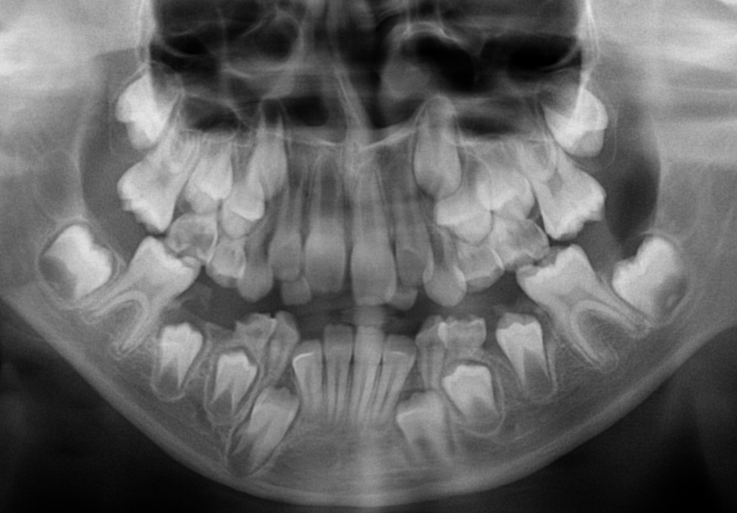

Pantomogram to panoramiczne zdjęcie RTG, które jest wykorzystywane przez lekarzy w różnych celach np. przy wizycie kontrolnej pozwala wykluczyć stany zapalne przy korzeniach zębów i wykryć pierwsze objawy różnych chorób jamy ustnej.

Jest pomocny także przy planowaniu leczenia: protetycznego, ortodontycznego czy chirurgicznego, a także przy kontroli wyrzynania się zębów stałych u dzieci.

Pantomogram umożliwia jednoczesne zobrazowanie zębów, szczęki i żuchwy, części zatoki szczękowej, podniebienia twardego i stawów skroniowo-żuchwowych.